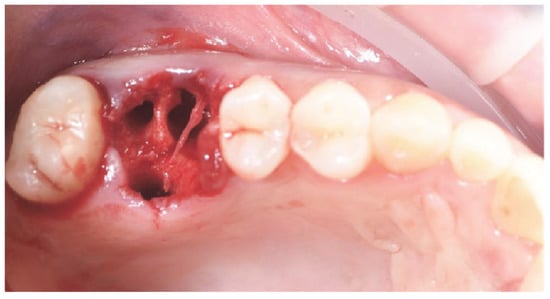

2.1. Socket Preservation Procedure